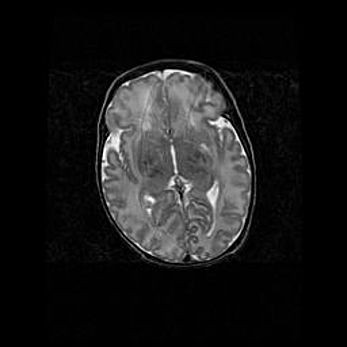

Церебральная ишемия II.

Возраст: 7 дней

Вес: 3350 г

Пол: женский

Окружность головы: 35 см

Срок гестации: 39 недель

Ишемия головного мозга – это состояние, которое развивается в ответ на кислородное голодание вследствие недостаточного мозгового кровообращения. У новорожденных она является следствием дефицита кислорода, что ведет к метаболическим расстройствам различной степени тяжести в тканях головного мозга, в том числе к развитию коагуляционных некрозов и гибели нейронов.